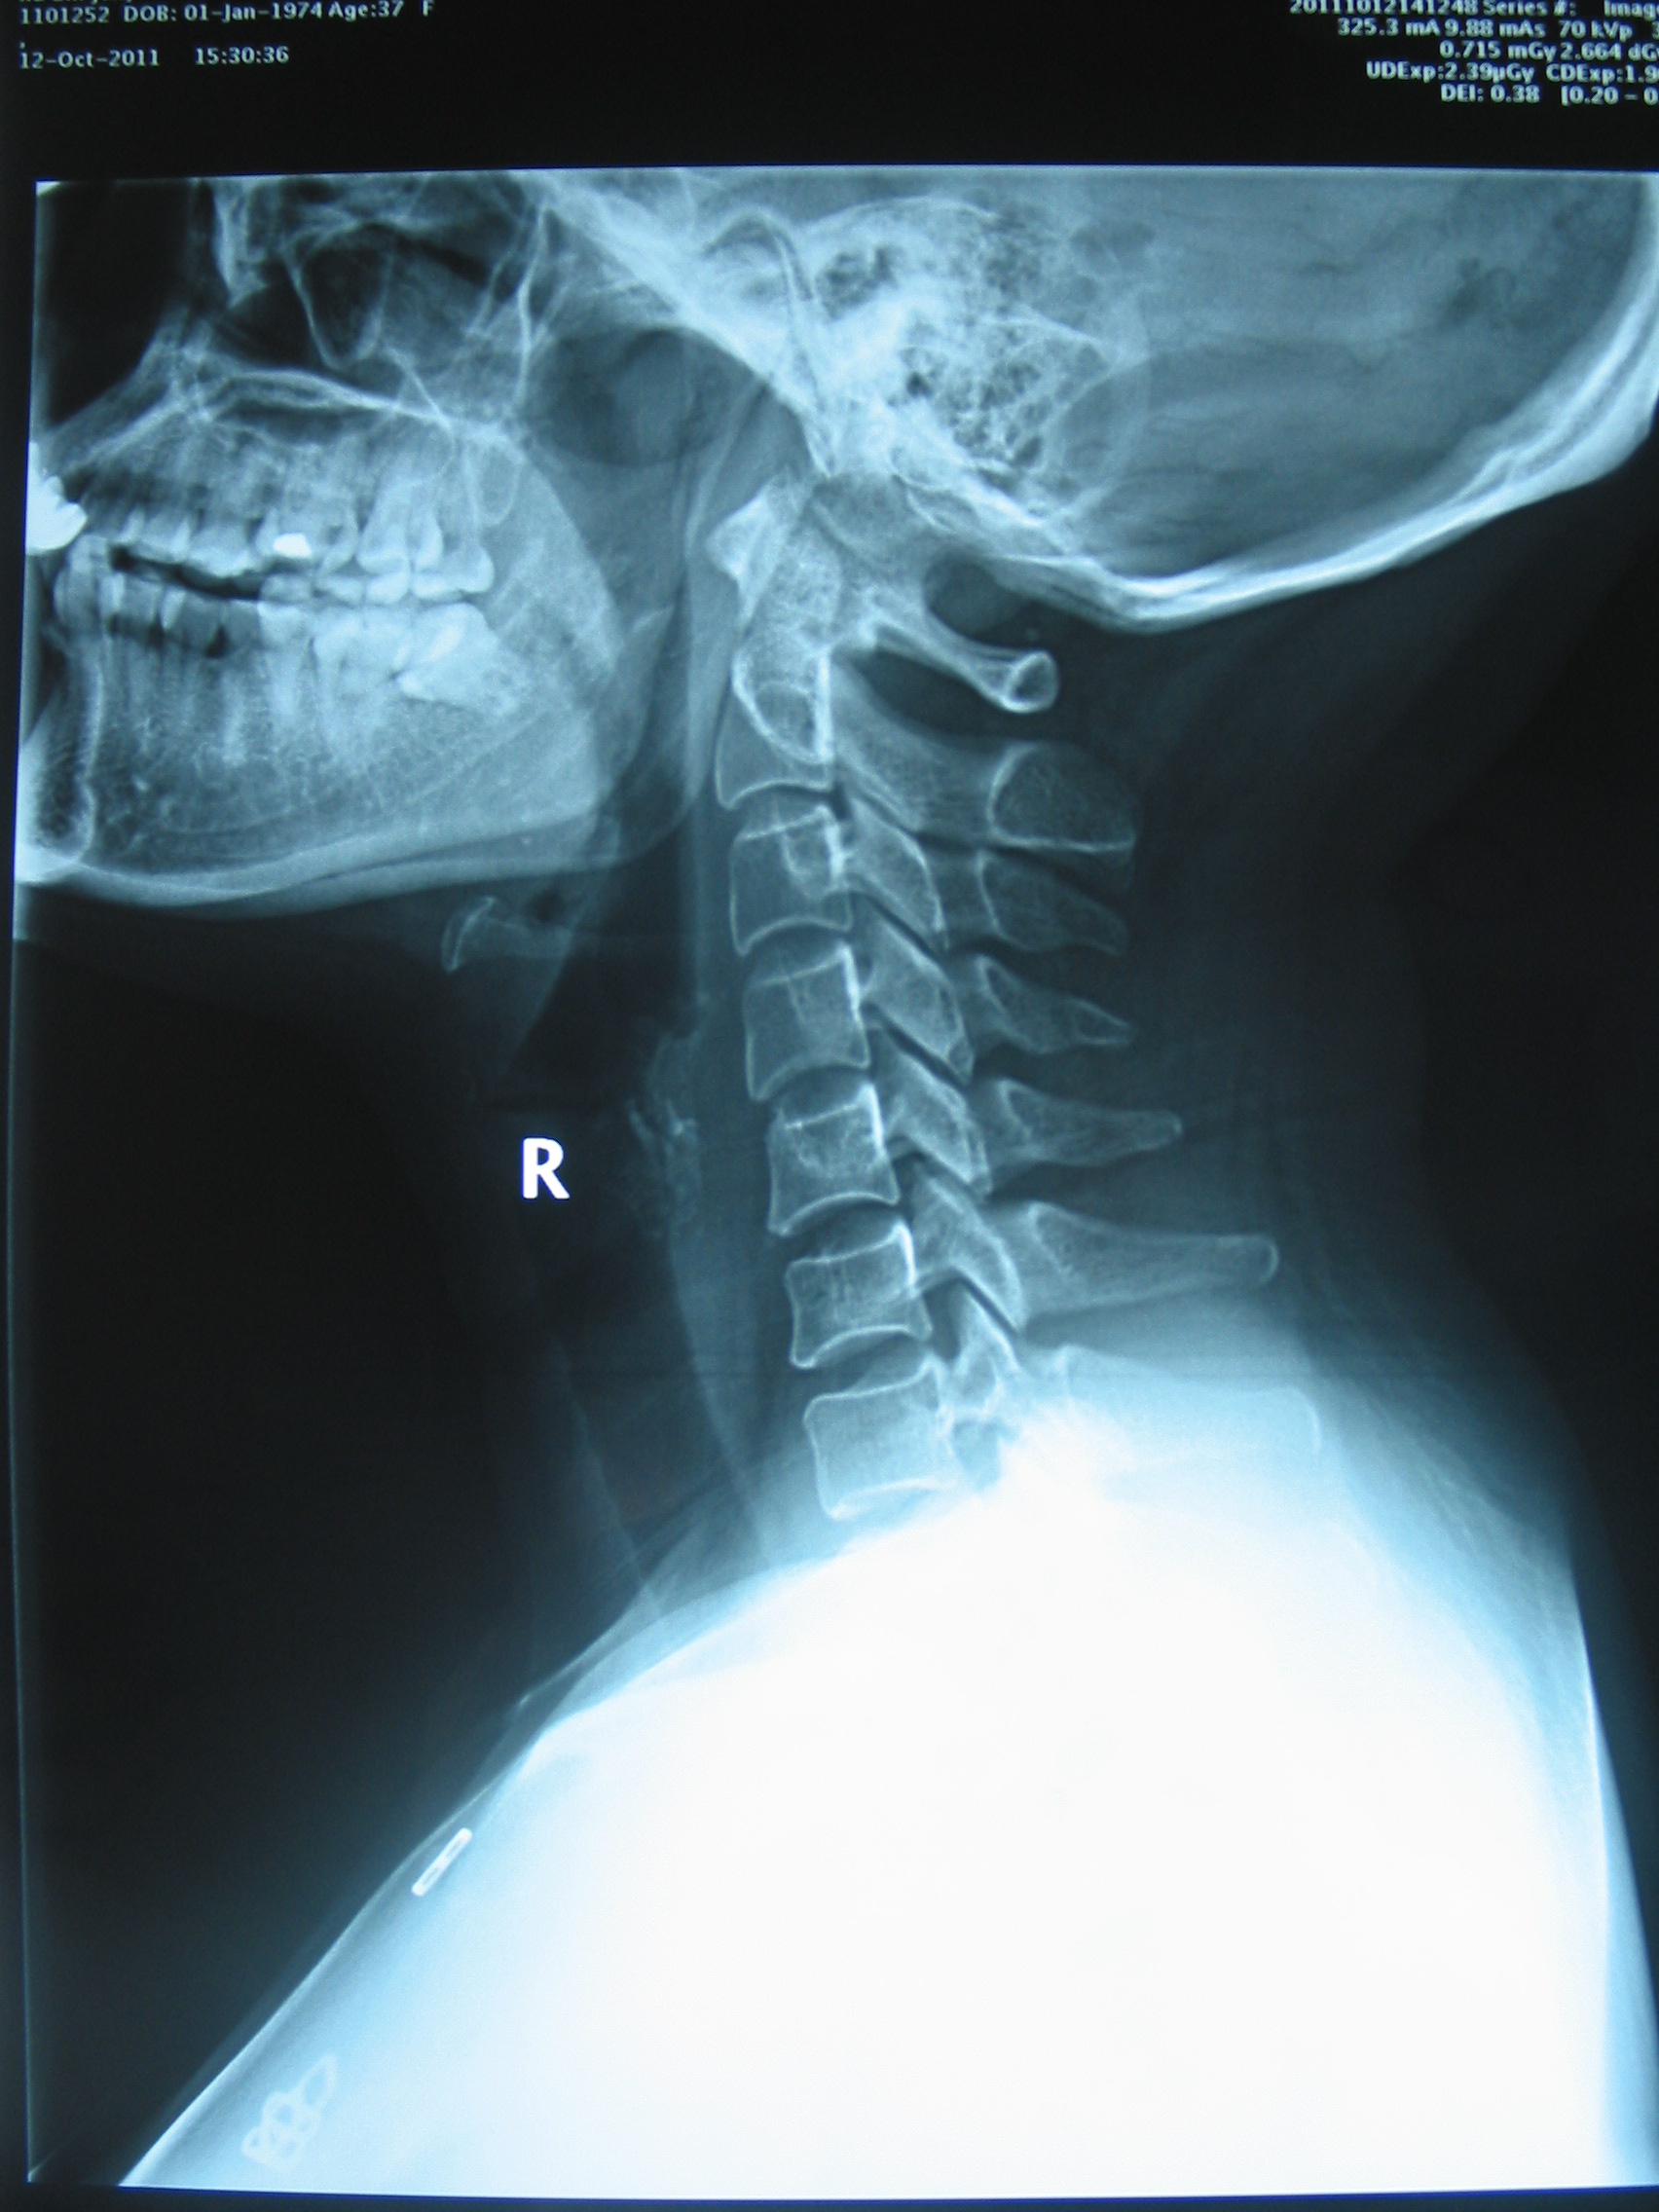

患者,女性,37岁,诉晚间卧床看电视过久,次日清晨头晕、恶心严重,遂至我院急诊就诊。予扩张血管、止吐等药物对症治疗,无明显疗效。查颈椎X线片,请我科门诊会诊。阅片:颈椎曲度异常,可见颈椎小关节紊乱征象(图X线片1,2, 颈椎正侧位治疗前(左侧))。予颈椎不定点旋转手法复位治疗,头晕恶心立即大部分缓解。隔日门诊复查仅残留偶发眩晕症状,复用旋转手法治疗,症状完全消失,复查X线,颈椎小关节紊乱已至正常(图X线片1,2,颈椎正侧位治疗后(右侧)),随访1月未见复发。

图2X线片